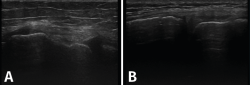

Tanto el ligamento lateral interno (LLI) como el ligamento lateral externo (LLE) pueden ser valorados por ecografía (Figura 7).

Figura 7. Corte coronal de una ecografía de rodilla. A: engrosamiento del ligamento lateral externo en la inserción proximal por un esguince de grado I; B: engrosamiento del ligamento lateral interno.